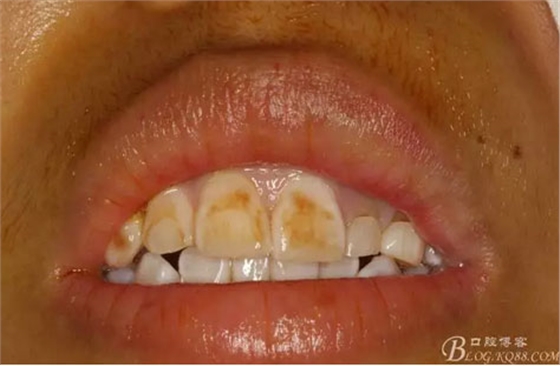

圖2.術前口內(nèi)像,左側(cè)乳Ⅱ、Ⅲ滯留,頸部楔形缺損,探針不敏感。左側(cè)乳Ⅱ、Ⅲ唇側(cè)粘膜膨隆,表面結(jié)節(jié)狀,捫診質(zhì)地堅硬,無波動。